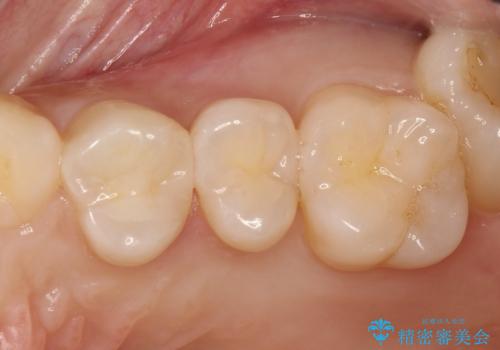

気づかないうちに大きな虫歯が 神経を保存し、セラミックで修復